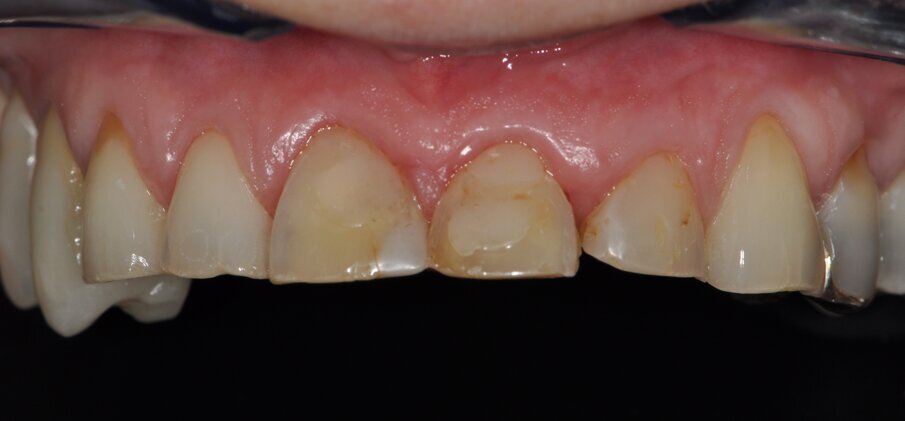

Fig. 3: Baseline situation for designing the esthetic anterior restorations following bite raising in the posterior region

In a first prosthetic treatment step, the posterior teeth were supplied with crowns (teeth 14, 26, 27, 37, and 47) and a bridge (teeth 17–15) in veneered zirconia. Teeth 32–42 were bleached and their incisal edges clinically lengthened by means of direct composite restorations (Essentia and G-Premio Bond; GC, Bad Homburg, Germany) in order to obtain a uniform esthetic result. Within the framework of the Celtra Campus Challenge, the patient could be offered a cost-effective and esthetic treatment offer upper jaw: Teeth 21 and 22 were restored with crowns and teeth 11, 12, 13, and 23 with veneers. In addition, teeth 24 and 25 received partial crowns. For the planning of the ceramic restorations, a wax-up was created and developed into a composite mock-up (Figs. 3 and 4) (Luxatemp; DMG). The tooth shade (A2) was selected based on the Vita Classic shade guide (Vita, Bad Säckingen, Germany).